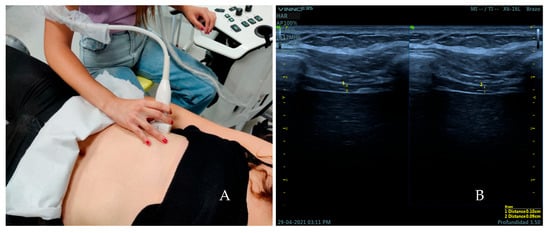

2.5. Measures